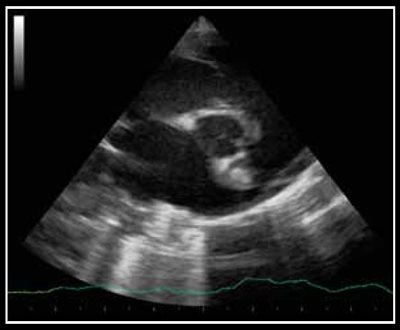

Photo 1 - Persistance du canal artériel visible en mode Doppler couleur sur une vue petit axe transaortique par abord parasternal droit.

Le canal artériel est visualisé dans 96 % des cas en mode bidimensionnel ou en mode Doppler couleur sur une coupe petit axe transaortique par abord parasternal droit (Photo 1), sur une coupe petit axe par abord parasternal crânial gauche (Photo 2), ou plus facilement sur une coupe longitudinale des gros vaisseaux (aorte et tronc pulmonaire) par abord parasternal crânial et dorsal gauche (Photo 3).